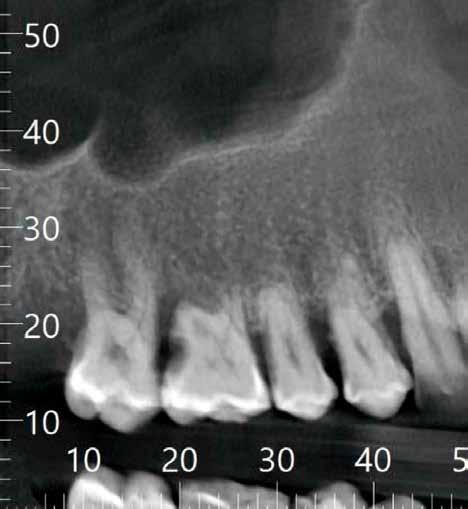

A műtéti tervezéshez mindkét esetben CBCT-felvételt használtunk, majd az utánkövetési időszakban periapikális röntgenfelvételekkel ellenőriztük az implantátumokat. A fogeltávolítást követően azonnali implantáció történt, az alveolus fala és az implantátum felszíne közt fennmaradó réseket csontpótlóval töltöttük ki. A három hónapos gyógyulás leteltével az ideiglenes koronákat eltávolítottuk, A-szilikonnal lenyomatot vettünk, majd három lítium-diszilikát és egy monolitikus cirkónium-dioxid korona készült. A páciensek utánkövetése mindkét esetben minimum tizenkét hónap volt, amelynek során valamennyi implantátumot klinikailag és radiológiailag is sikeresnek ítéltünk az osszeointegráció, a marginális csont stabilitása és a periimplantáris szövetek egészsége tekintetében.

A végleges ragasztást követően röntgenfelvételt készítettünk, amelyet összevetettünk a közvetlenül a műtét után készült felvételekkel: a marginális csontszint változatlan volt. A pácienseket 14 hónapon keresztül rendszeresen visszahívtuk. Klinikai és röntgenvizsgálattal sem tapasztaltunk komplikációt (12. a–b ábrák)

Tanulmányunk célja összesen négy, rágó területre beültetett kétrészes Zi ceramic implant® kerámiaimplantátum (Neodent) teljesítményének értékelése volt. A legalább tizenkét hónapos utánkövetés alatt egyetlen esetben sem tapasztaltunk technikai vagy biológiai szövődményt, amely bizonyítja az implantátum osszeointegrációjának klinikai és radiológiai sikerét, valamint a lágy- és keményszövetek volumenének stabilitását. Eredményeink összhangban vannak más, azonos implantátumokkal és hasonló utánkövetési periódussal készült tanulmányok tapasztalataival [8, 10]. Korábbi, állatokon végzett vizsgálatok kimutatták, hogy a cirkónium-dioxid implantátumok osszeointegrációja megbízható és biztonságos, még különböző terhelési viszonyok mellett is [11, 12]. Mint azt korábban említettük, jelen tanulmányban mind a négy implantátum sikeresen osszeointegrálódott a vizsgált tizenkét hónap alatt.

Medentika® ÉLETHOSSZIG TARTÓ GARANCIA

Korábbi tanulmányok kimutatták, hogy a cirkónium-dioxid felületek hajlama a biofilmképződésre kisebb, mint a titánfelületeké [13]. Jelen vizsgálatban gyulladásos folyamatoktól mentes és egészséges megjelenésű periimplantáris szöveteket lehetett megfigyelni (12. a–b ábra). Egy másik, a jelen tanulmányban alkalmazott implantátumrendszerrel végzett prospektív klinikai vizsgálat kimutatta, hogy legalább tizenkét hónapos utánkövetés mellett sem volt tapasztalható kóros elváltozás a periimplantáris lágyszövetekben [8]. Ugyanez a tanulmány, egy további prospektív klinikai vizsgálat, valamint saját eredményeink egybehangzóan azt mutatják, hogy a marginális csont szintje a megfigyelt idő alatt stabil volt [8, 10, 14]. Az itt bemutatott két páciens kerámiaimplantátumokat kapott a felső moláris régióba. Komplikációkat, mint például az implantátum vagy a felépítmény törése, nem tapasztaltunk. Ez a tény megerősíti más tanulmányok megállapításait is, amelyek szerint a kerámia fogászati implantátumok gyártására az ittriummal stabilizált cirkónium-dioxid (YTZP) a legalkalmasabb. Az YTZP esztétikai és biológiai előnyei mellett a korrózióval, kopással és rágóerőkkel szembeni nagyfokú ellenálló képessége is kimagasló [15]. Érdemes megemlíteni, hogy jelen tanulmány tizenkét hónapos követési időszakot ölel fel, amely rövidnek számít. Azonban ezen időszak alatt nem tapasztaltunk klinikai vagy biológiai szövődményt, külö-